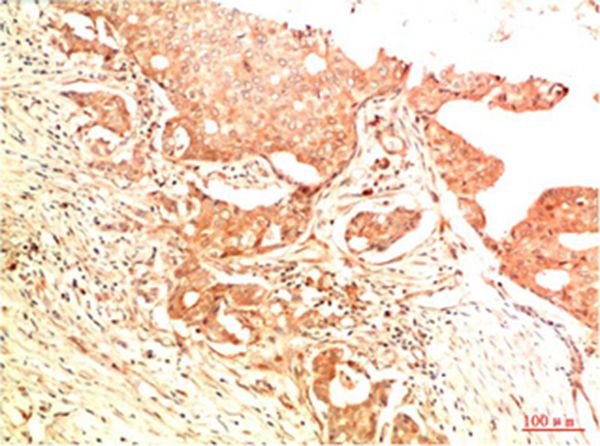

Immunohistochemical analysis of paraffin-embedded Human Breast Carcinoma Tissue using Acetyl P53(K382) Mouse mAb diluted at 1:200.